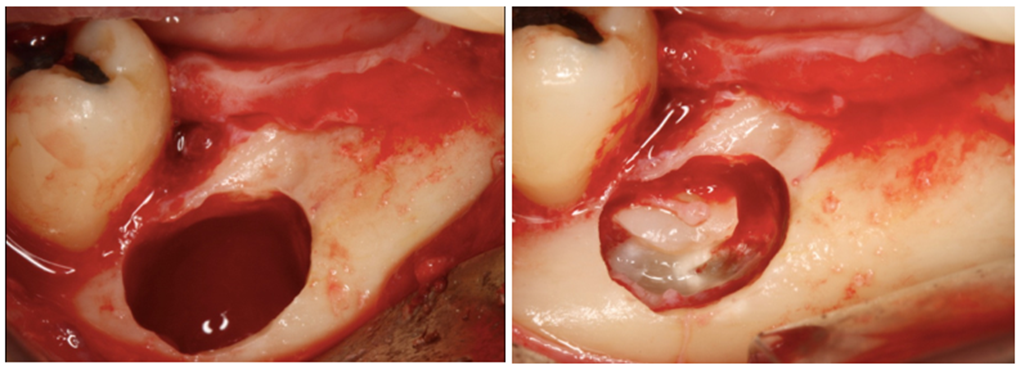

The option, in this case, was for a coronoidectomy on the impacted teeth through vestibular access and odontosection, followed by filling with inorganic bovine bone (Bio-oss) and covering with a slow-resorption collagen membrane (Bio-Gide) (figures 6 and 7). After 6 months 2 implants were installed on each side. Two implants showed intimate contact with the impacted teeth. After 60 days the patient was rehabilitated with metal-ceramic prostheses with splinted implants.

Figures 7 and 8: Transoperative images of coronoidectomy.

Under local anestesia, the crown was removed through a vestibular approach and odontosection. An implant was immediately installed transfixing the region where the crown was removed by locking in the bone apical to this location. The gap between the bone and the implant was filled with Bio-oss Collagen (figure 11). Two implants were installed in the positions corresponding to the lower left molars.